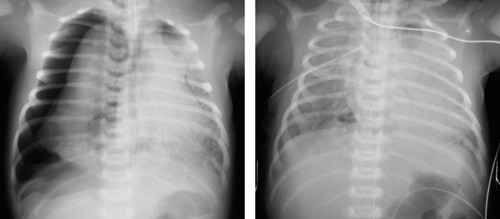

Det ble gjort en prospektiv registrering av pulmonal luftlekkasje hos barn født i perioden 1989 – 2006 og innlagt i neonatalenheten, Sykehuset i Vestfold, Tønsberg. Sykehuset hadde i den aktuelle perioden 90 % av fødslene i fylket, mens 0,7 % ble født ved regionsykehus og de resterende 9 % ved andre sentral- og lokalsykehus. Materialet er således nært populasjonsbasert. Luftlekkasje ble diagnostisert røntgenologisk ut fra pasientens sykdomsbilde (fig 1). Alle bilder ble vurdert av to radiologer, og minst én av dem, som regel begge, var spesialist i radiologi.

Neonatal pulmonal luftlekkasje ble diagnostisert hos 1,4 per 1 000 levendefødte. Pneumothorax var den dominerende formen (95 %). Symptomgivende luftlekkasje er således relativt sjeldent hos nyfødte. Luftlekkasje ville imidlertid blitt påvist langt hyppigere dersom man hadde tatt røntgen thorax av alle nyfødte (også tilsynelatende friske) (1). Ved de første åndedragene genereres høye transpulmonale trykkvariasjoner i lungene, og alveolruptur med luftlekkasje kan inntreffe som følge av alveolær overdistensjon. Dette illustreres i det aktuelle materialet, hvor tilstanden ofte oppsto spontant og ble diagnostisert kort tid etter fødselen (røntgenundersøkelse pga. respirasjonssymptomer hos barn født uten komplikasjoner og ikke utsatt for intervensjon). Flesteparten var barn født til termin. Hos disse kan muskelkraften ved de første åndedragene være stor, og store intramurale trykkforskjeller genereres. Overvekten av gutter er overensstemmende med funn gjort i en dansk studie (4).